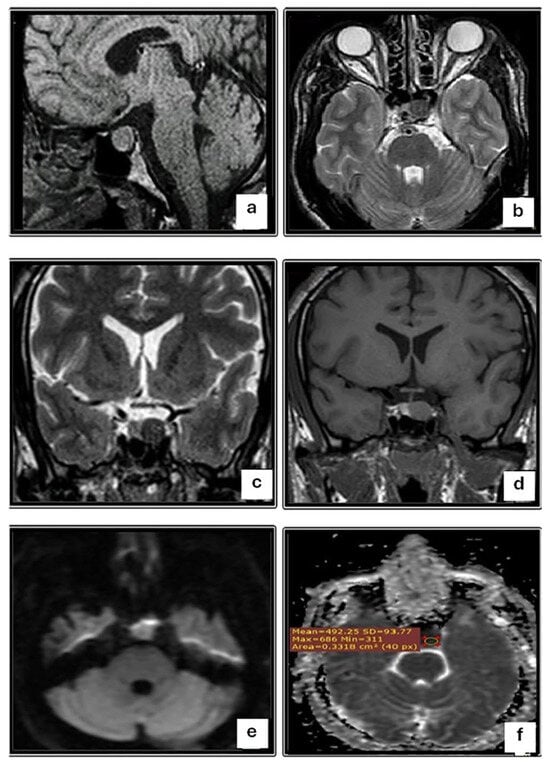

| T2W1 | 0.001 | |

| Iso-intense | 0 (0) | |

| Hypo-intense | 12 (28.6) | |

| Hyper-intense | 33 (73.3) |

| DWI (b 100) | <0.001 | |||

| Iso-intense | 9 (20.0) | 9 (33.3) | 0 (0) | |

| Hypo-intense | 15 (33.3) | 0 (0) | 15 (83.3) | |

| Hyper-intense | 21 (46.7) | 18 (66.7) | 3 (16.7) | |

| ADC map | 0.004 | |||

| Hypo-intense | 21 (46.7) | 18 (66.7) | 3 (16.7) | |

| Hyper-intense | 15 (33.3) | 0 (0) | 15 (83.3) | |

| ADC value, Mean ±SD (range) | 0.72 ± 0.25 (0.40–1.10) | 0.54 ± 0.19 (0.42–0.90) | 0.95 ± 0.08 (0.90–1.10) | 0.008 |